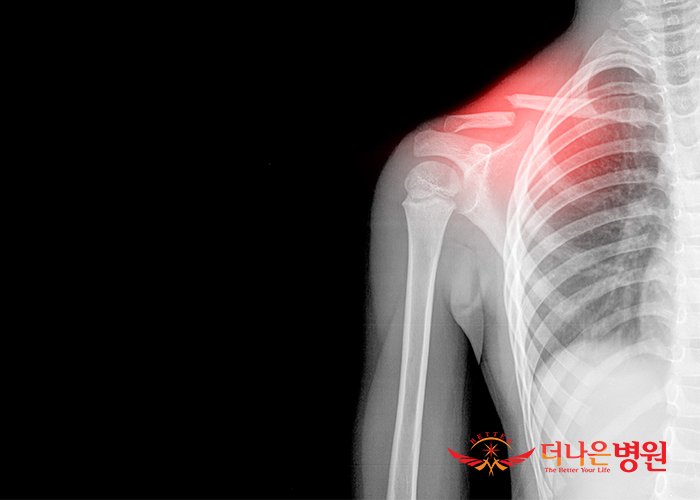

흉쇄관절에 있는 관절원판은 관절을 내측강과 외측강으로 분리시킵니다. 편평한 섬유연골인 원판은 아래쪽으로는 쇄골면의 외측 가장자리 근처에 부착되고 위쪽으로는 쇄골두와 쇄골간인대에 부착되고, 원판의 나머지 바깥쪽 가장자리는 관절낭의 안쪽면에 부착되게 됩니다. 원판은 관절면의 접촉영역을 증가시켜 관절내부에 대한 충격 흡수의 기능을 수행하게 됩니다. 이러한 충격 흡수의 기전에 의해 흉쇄관절에는 퇴행성관절염이 거의 나타나지 않습니다. 앞서 말했듯 흉쇄관절에서의 안정성은 이 관절을 에워싸고 있는 관절주위 결합조직들에 의해 이루어집니다. 이러한 결합조직의 단단한 고정은 쇄골을 통해 내측방향으로 전달된 큰 힘에 의해 흉쇄관절의 탈구 대신 쇄골 간부의 골절을 유발하게 됩니다. 쇄골골절은 30세 이하의 남성에서는 아주 흔히 일어날 수 있습니다. 이러한 골절의 대부분은 접촉이 많은 스포츠나 교통사고에 의해 유발되게 됩니다.